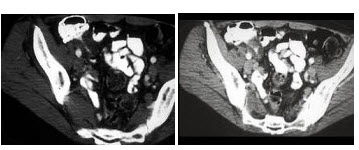

男,42岁,右下腹痛、腹胀半年,无浅表淋巴结肿大,影像检查如图,最可能的诊断是()

A、淋巴瘤

B、结肠癌

C、Crohn病

D、肠结核

E、腹膜后纤维化

C